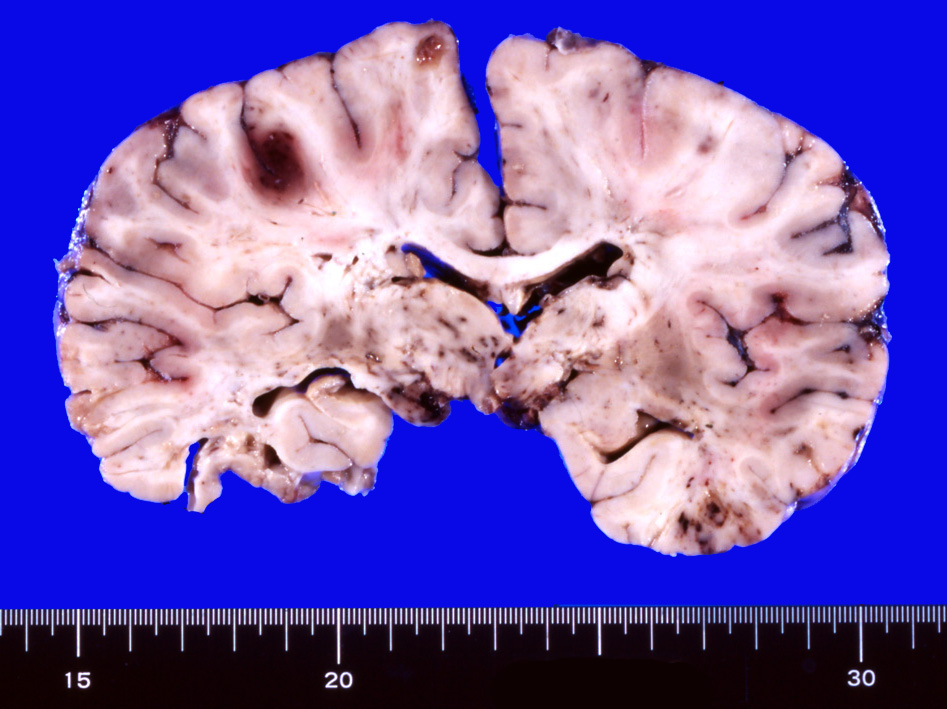

剖検肉眼病理所見

多発脳梗塞, 点在する出血壊死, 壊死に陥った組織が欠落している。